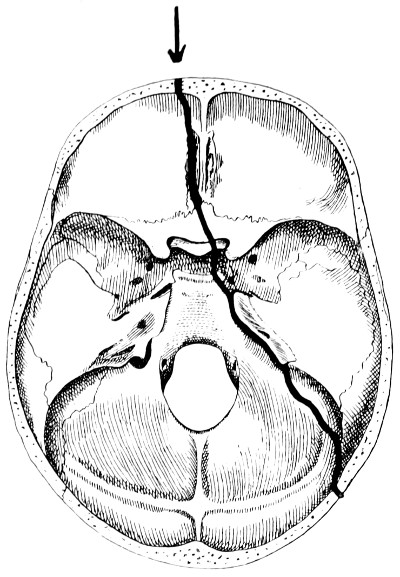

28. Illustrating the lines along which forces received on the vault are transmitted to the base 69

32-37. The lines pursued by basic fractures 83-8

38 A and B. To illustrate the probable source of profuse hæmorrhage from the ear 97